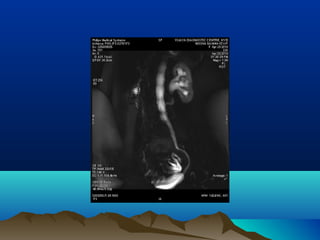

โ€ข MR UROGRAPHY

โ€ข TO DIFFERENTIATE PHYSIOLOGICAL FROM CALCULUS

โ€ข HYDRONEPHROSIS

โ€ข DOUBLE KINK SIGN โ€“ SPINDLE SHAPED PELVIC URETER